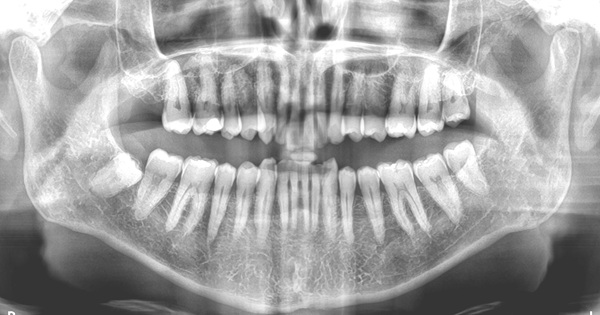

2024年時の院長の口腔状態